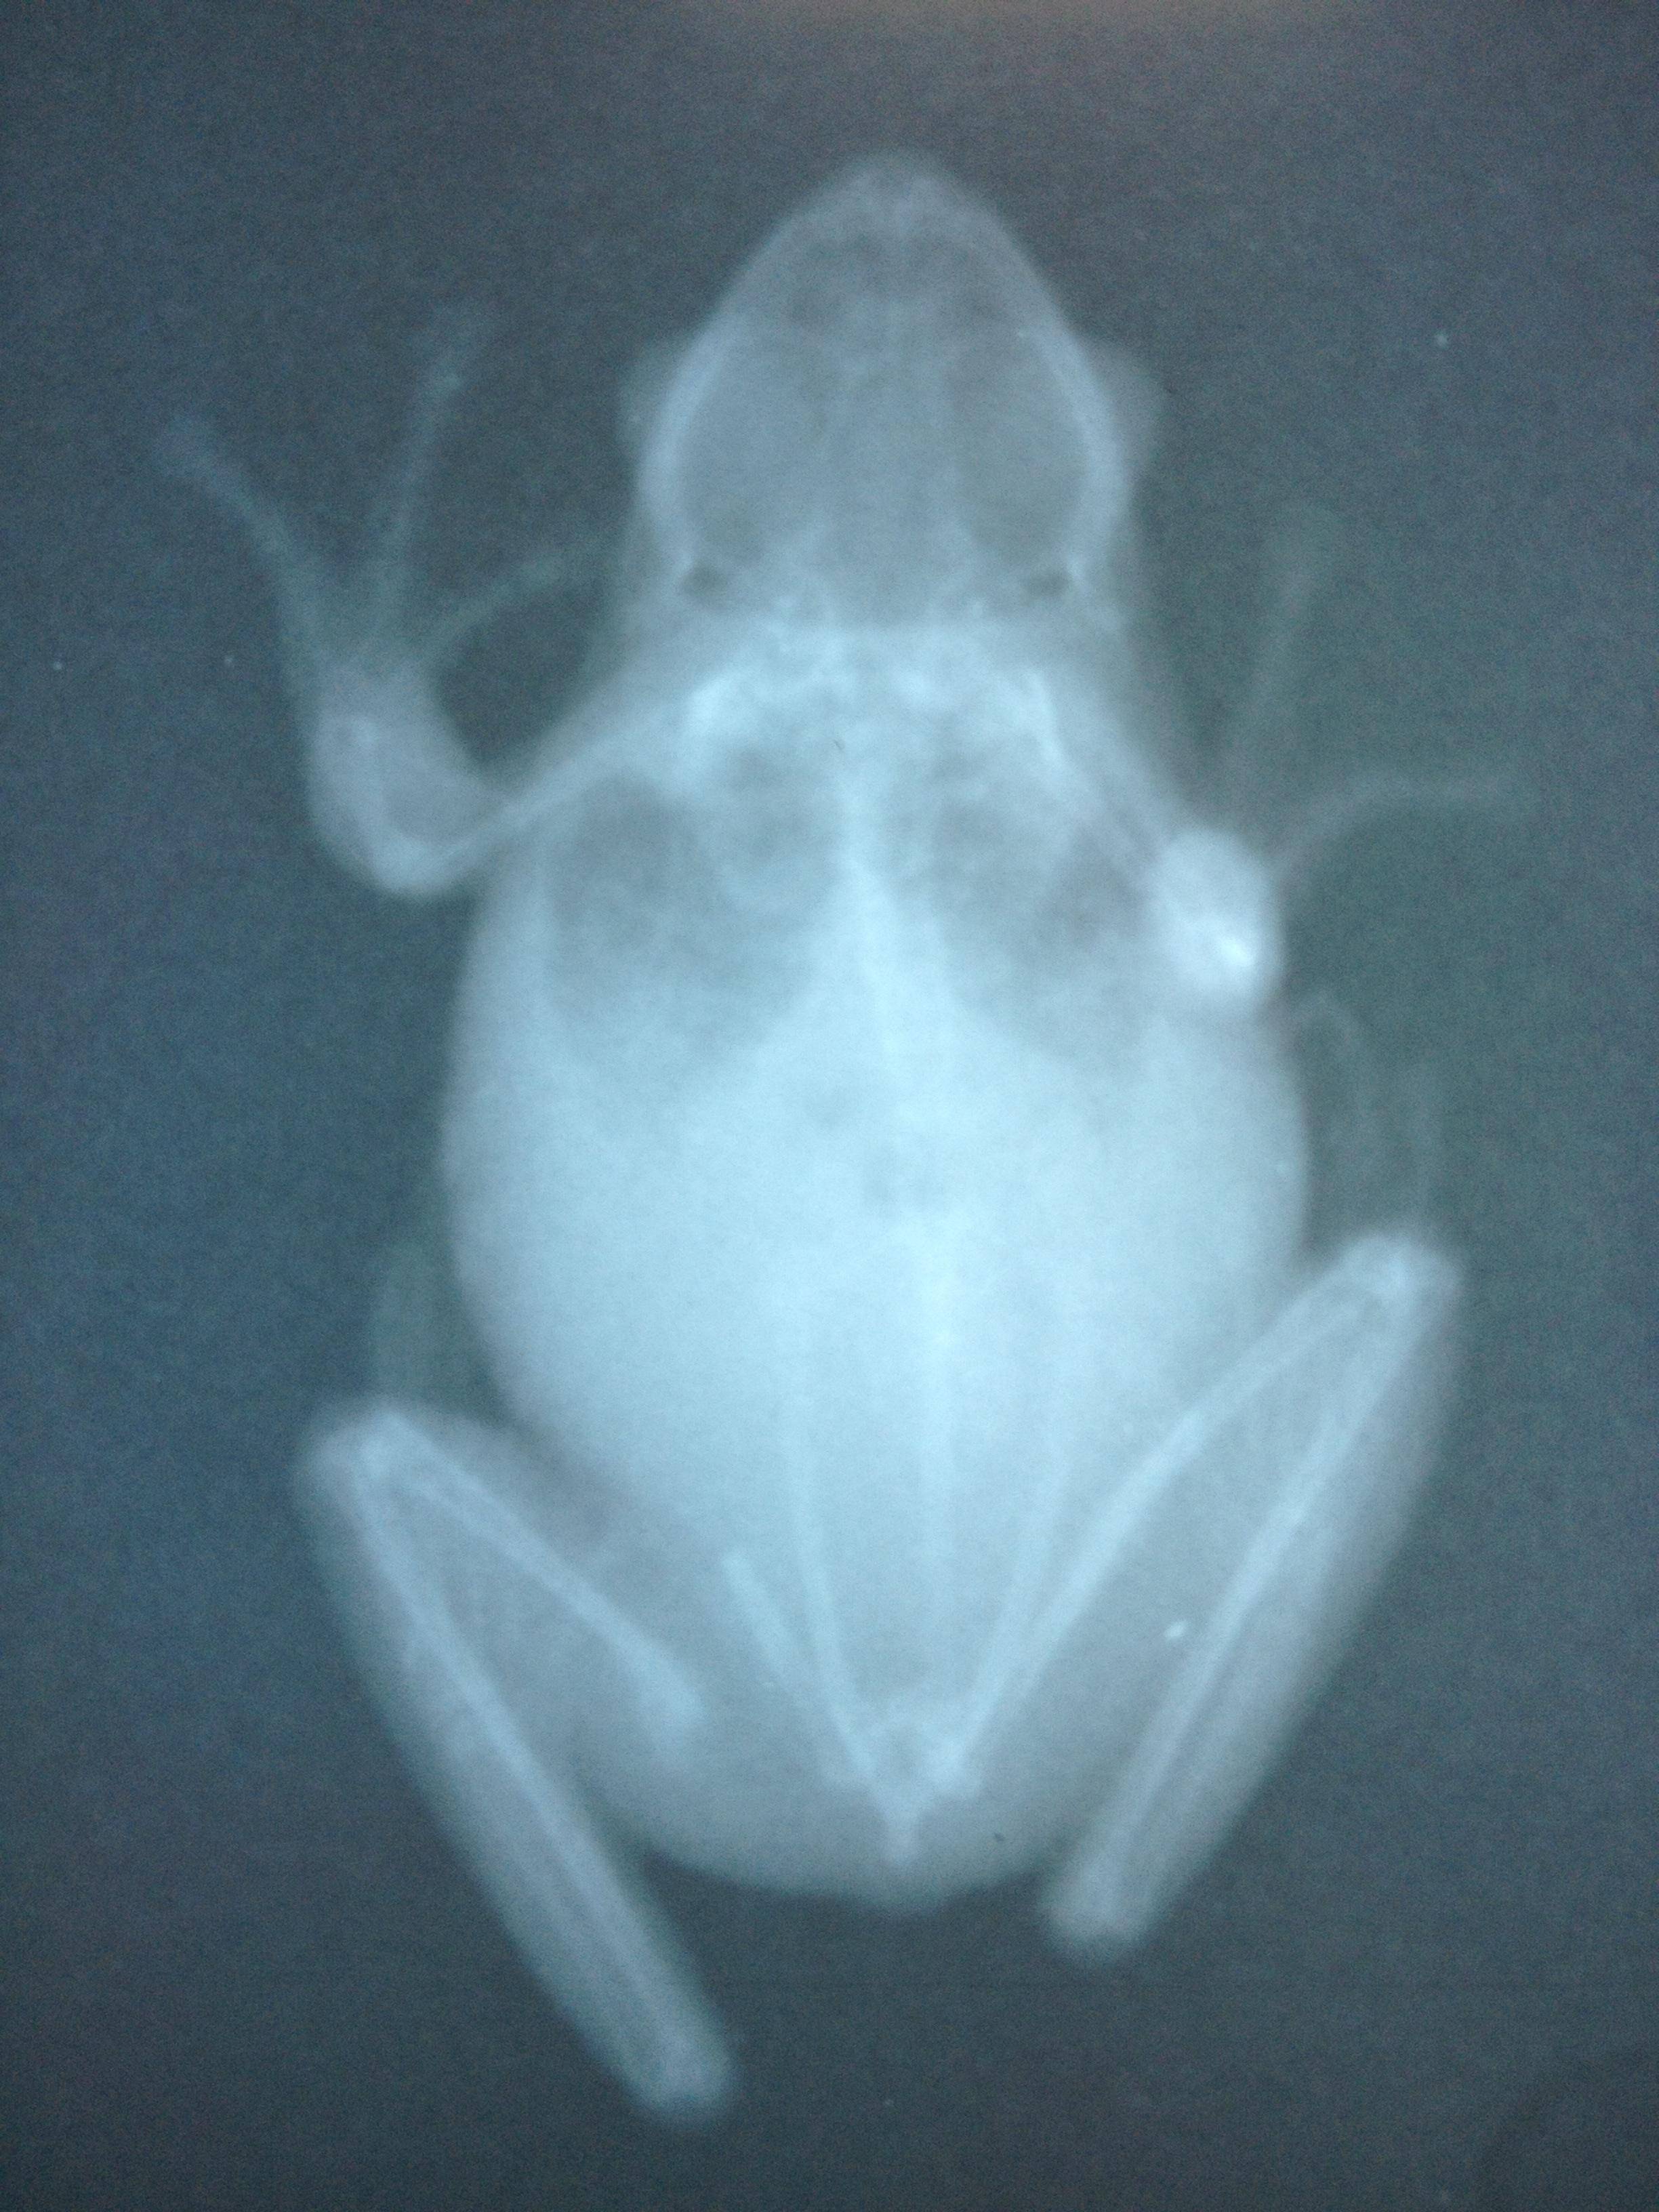

Alright, so the vet squeezed me in once I told them I thought her leg was broken. Didn't even have to wait very long too. Her weight is 13g, down from 16 when I took her 2 months ago. He did inform me that he did use Panacur last time for the worms, and he did give her some more. He thinks that since she had nothing but pinworms last time that maybe some were in her muscles and seaped out after the others were gone. She does infact have a broken leg

Attachment 53470Attachment 53471

He told me if her bones were large enough he could stick a pin in and set it, but since she is so tiny, she will just have to heal on her own. He did say her bones look great so I guess that's a plus (besides the broken one). I did pick up some water treatment stuff

I guess they didn't load but here are some pics I thought everyone would like to see!